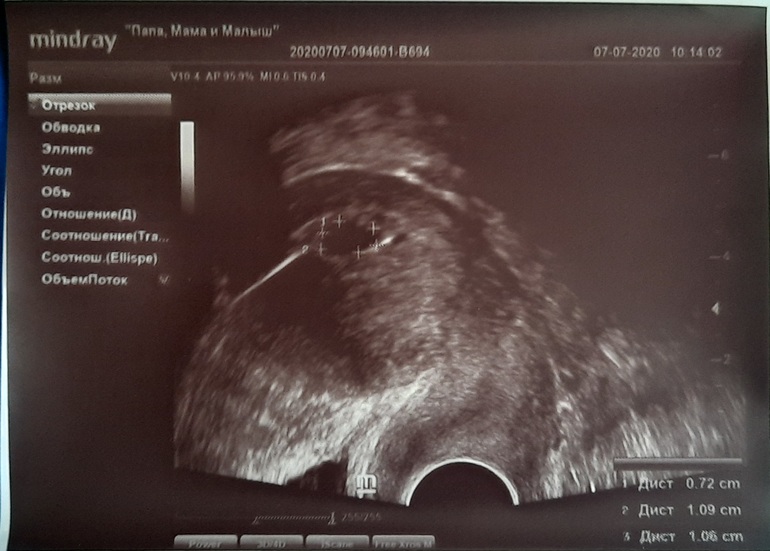

22дпп УЗИ

Сегодня, на 22 дпп назначено было узи. Я так надеялась увидеть хотя бы желточный мешочек! Ре сказала, что вроде бы что то там виднеется, может быть, но ещё не точно, короче пока визуализируется только одно ПЯ 10 мм, она говорит всё в норме, приходить в следующую пятницу смотреться ещё, подарила фото в милом конвертике "моё первое фото", а я вот сижу и переживаю! У многих на этом сроке жм видно, а то и эмбрион, а у меня ничего( Нет, ну я бы не истерила так, если бы в прошлый раз не было анэмбрионии, а теперь до ужаса боюсь повторения ситуации( Успокаиваю себя, медитирую каждый день, отвлекаюсь, но как же хотелось сегодня увидеть хотя бы жм! Как я на следующей неделе на узи пойду, не представляю, уже боюсь, боюсь опять увидеть пустоту!